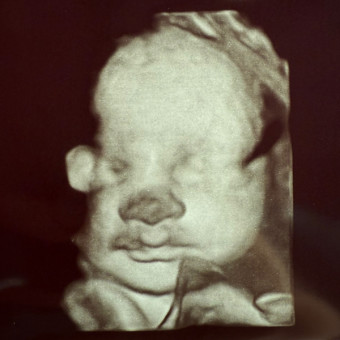

Baby Slavens

Layla Marie & Riley Slavens

Whittier, NC

November 2025